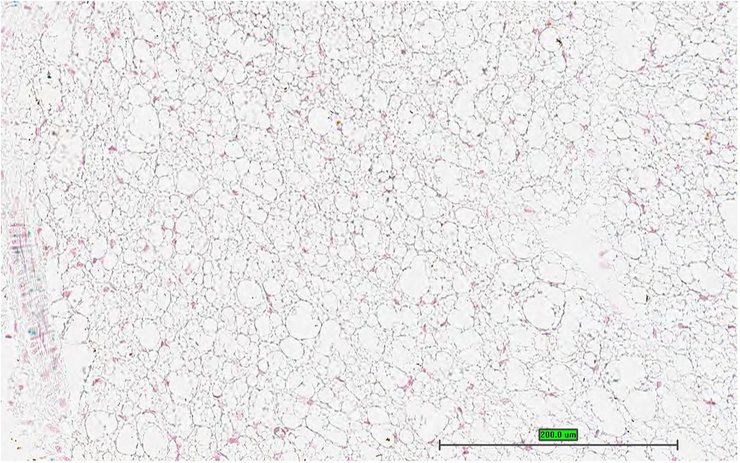

TS28: gonadal fat pad Present UC Davis_1863179

Specimen UC Davis_1863180: postnatal adult; Cilk1tm1b(KOMP)Mbp/Cilk1+ (more )

Structure Level Pattern Image Note

TS28: mesenteric adipose tissue Present UC Davis_1863180